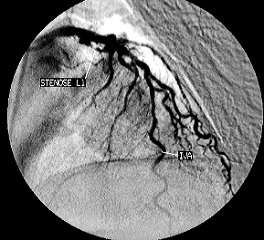

Figura 7. Coronarografie stanga a), dreapta b) stenoze multiple ateromatoase

Angiografia coronariana cu substanta de contrast efectuata la intervale de timp va arata gradul de evolutivitate al obstructiei coronariene si modul de dezvoltare a circulatiei colaterale (Dr. R. R. Mateescu, 2005).

a)

b)

Figura 8. angiografie coronariana: a) artera coronara normala; b) artera coronara cu ischemie.